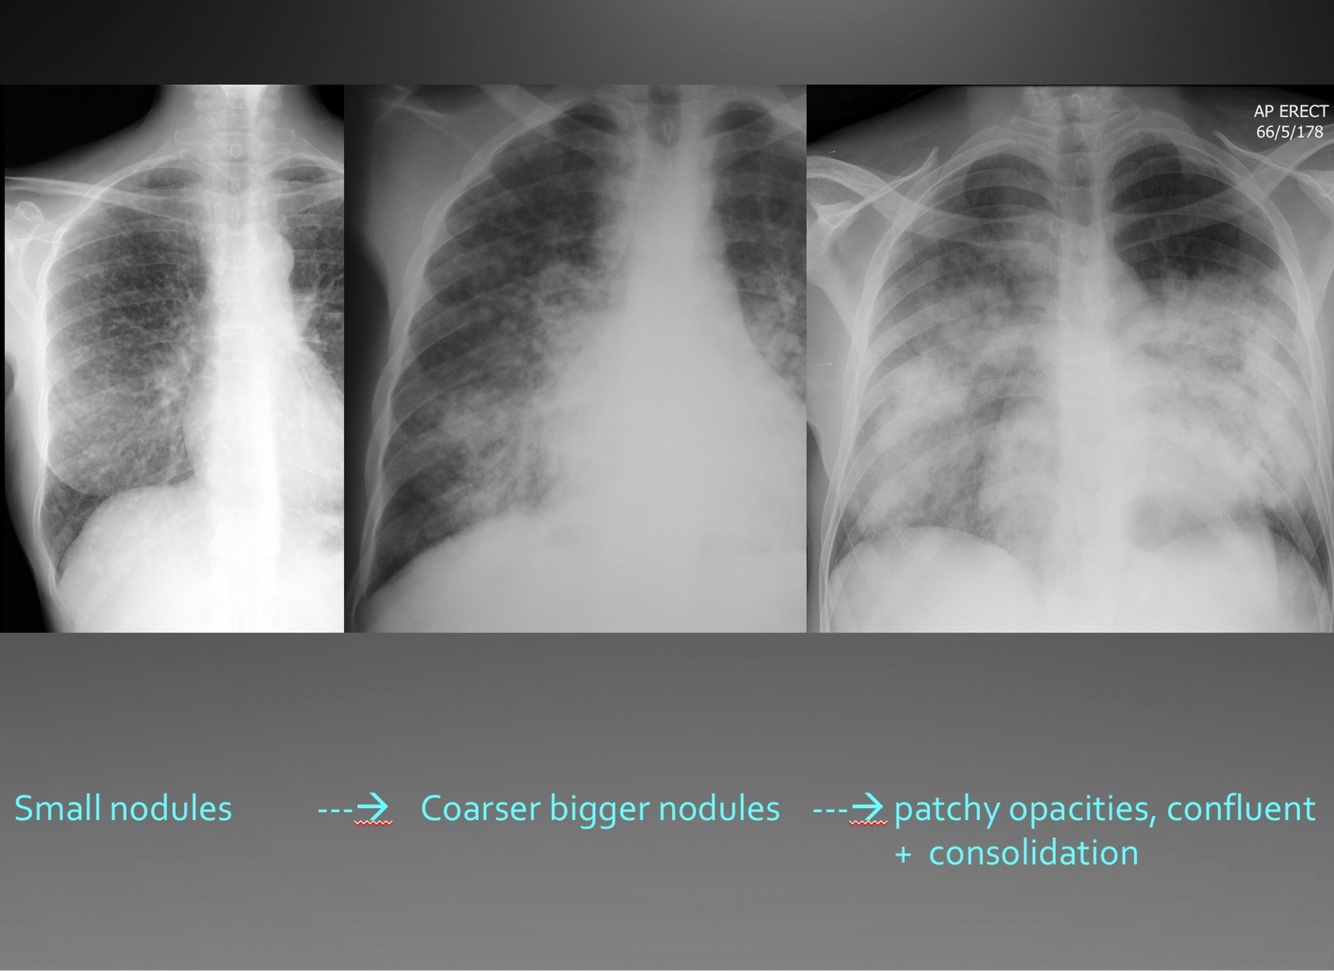

Explain picture

Nodular pattern